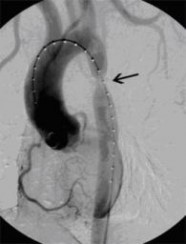

Aortenkoarktationsstenose vor Stentimplantation

(Bild 1 von 4)

Aortenkoarktationsstenose nach Stentimplantation

(Bild 2 von 4)